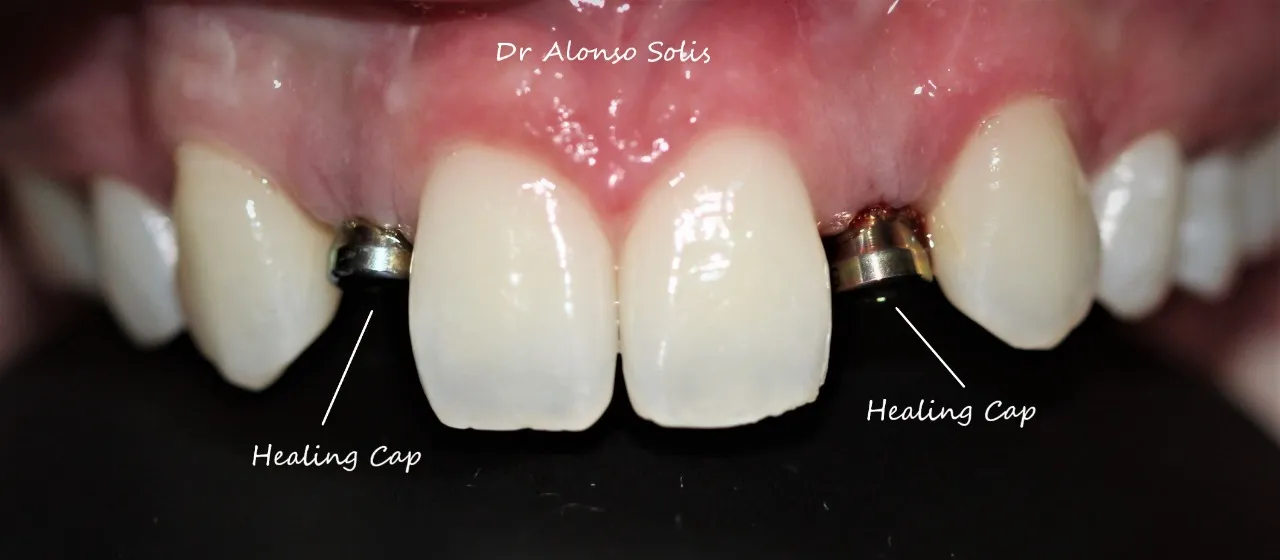

Caso 2

Paciente femenina, 19 años, con agenesia dental (ausencia de piezas de nacimiento), se realiza colocación de 2 implantes en piezas laterales, confección de provisionales y se esperan 4 meses para la colocación de piezas permanentes sobre implantes.